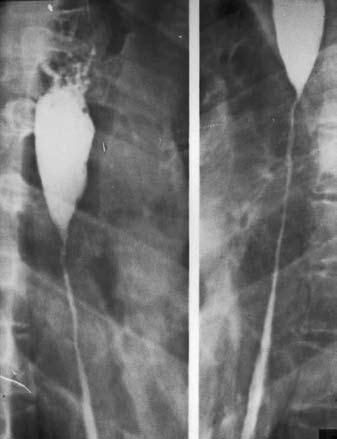

Рис. 27. Рентгенограмма пищевода при его послеожоговом рубцовом сужении . На снимке видны супрастенотическое расширение конической формы и протяженная стриктура средне– и нижнегрудного отделов пищевода.